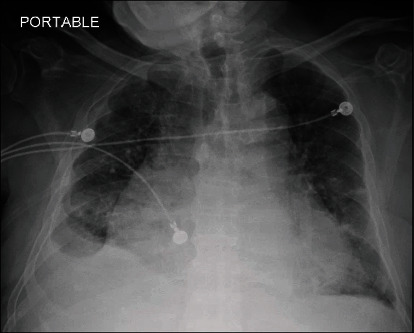

Uremic pericardial effusion and pericarditis in end-stage kidney disease patients remain one of the causes responsible for high rates of morbidity and occasional mortality. While clinical presentation could be variable, clinicians should have a high index of suspicion for uremic pericarditis especially in patients who miss their dialysis sessions. We present a 77-year-old man with end-stage renal disease on dialysis diagnosed with pericarditis and large pericardial effusion complicated by cardiac tamponade and shock. He underwent urgent pericardiocentesis with clinical improvement. The course of the disease can be complicated by shock with multiorgan failure, particularly the liver. The presentation is relatively acute requiring a high level of suspicion, urgent diagnosis, and management to reduce mortality. As the geriatric population increases with associated comorbid conditions, it would be expected that patients undergoing dialysis would increase. Given the uncommon nature of the disease and how these patients have been managed by multiple specialties and care providers, it is important to consider dialysis-related complications in all patients with end-stage renal disease presenting with dyspnea.